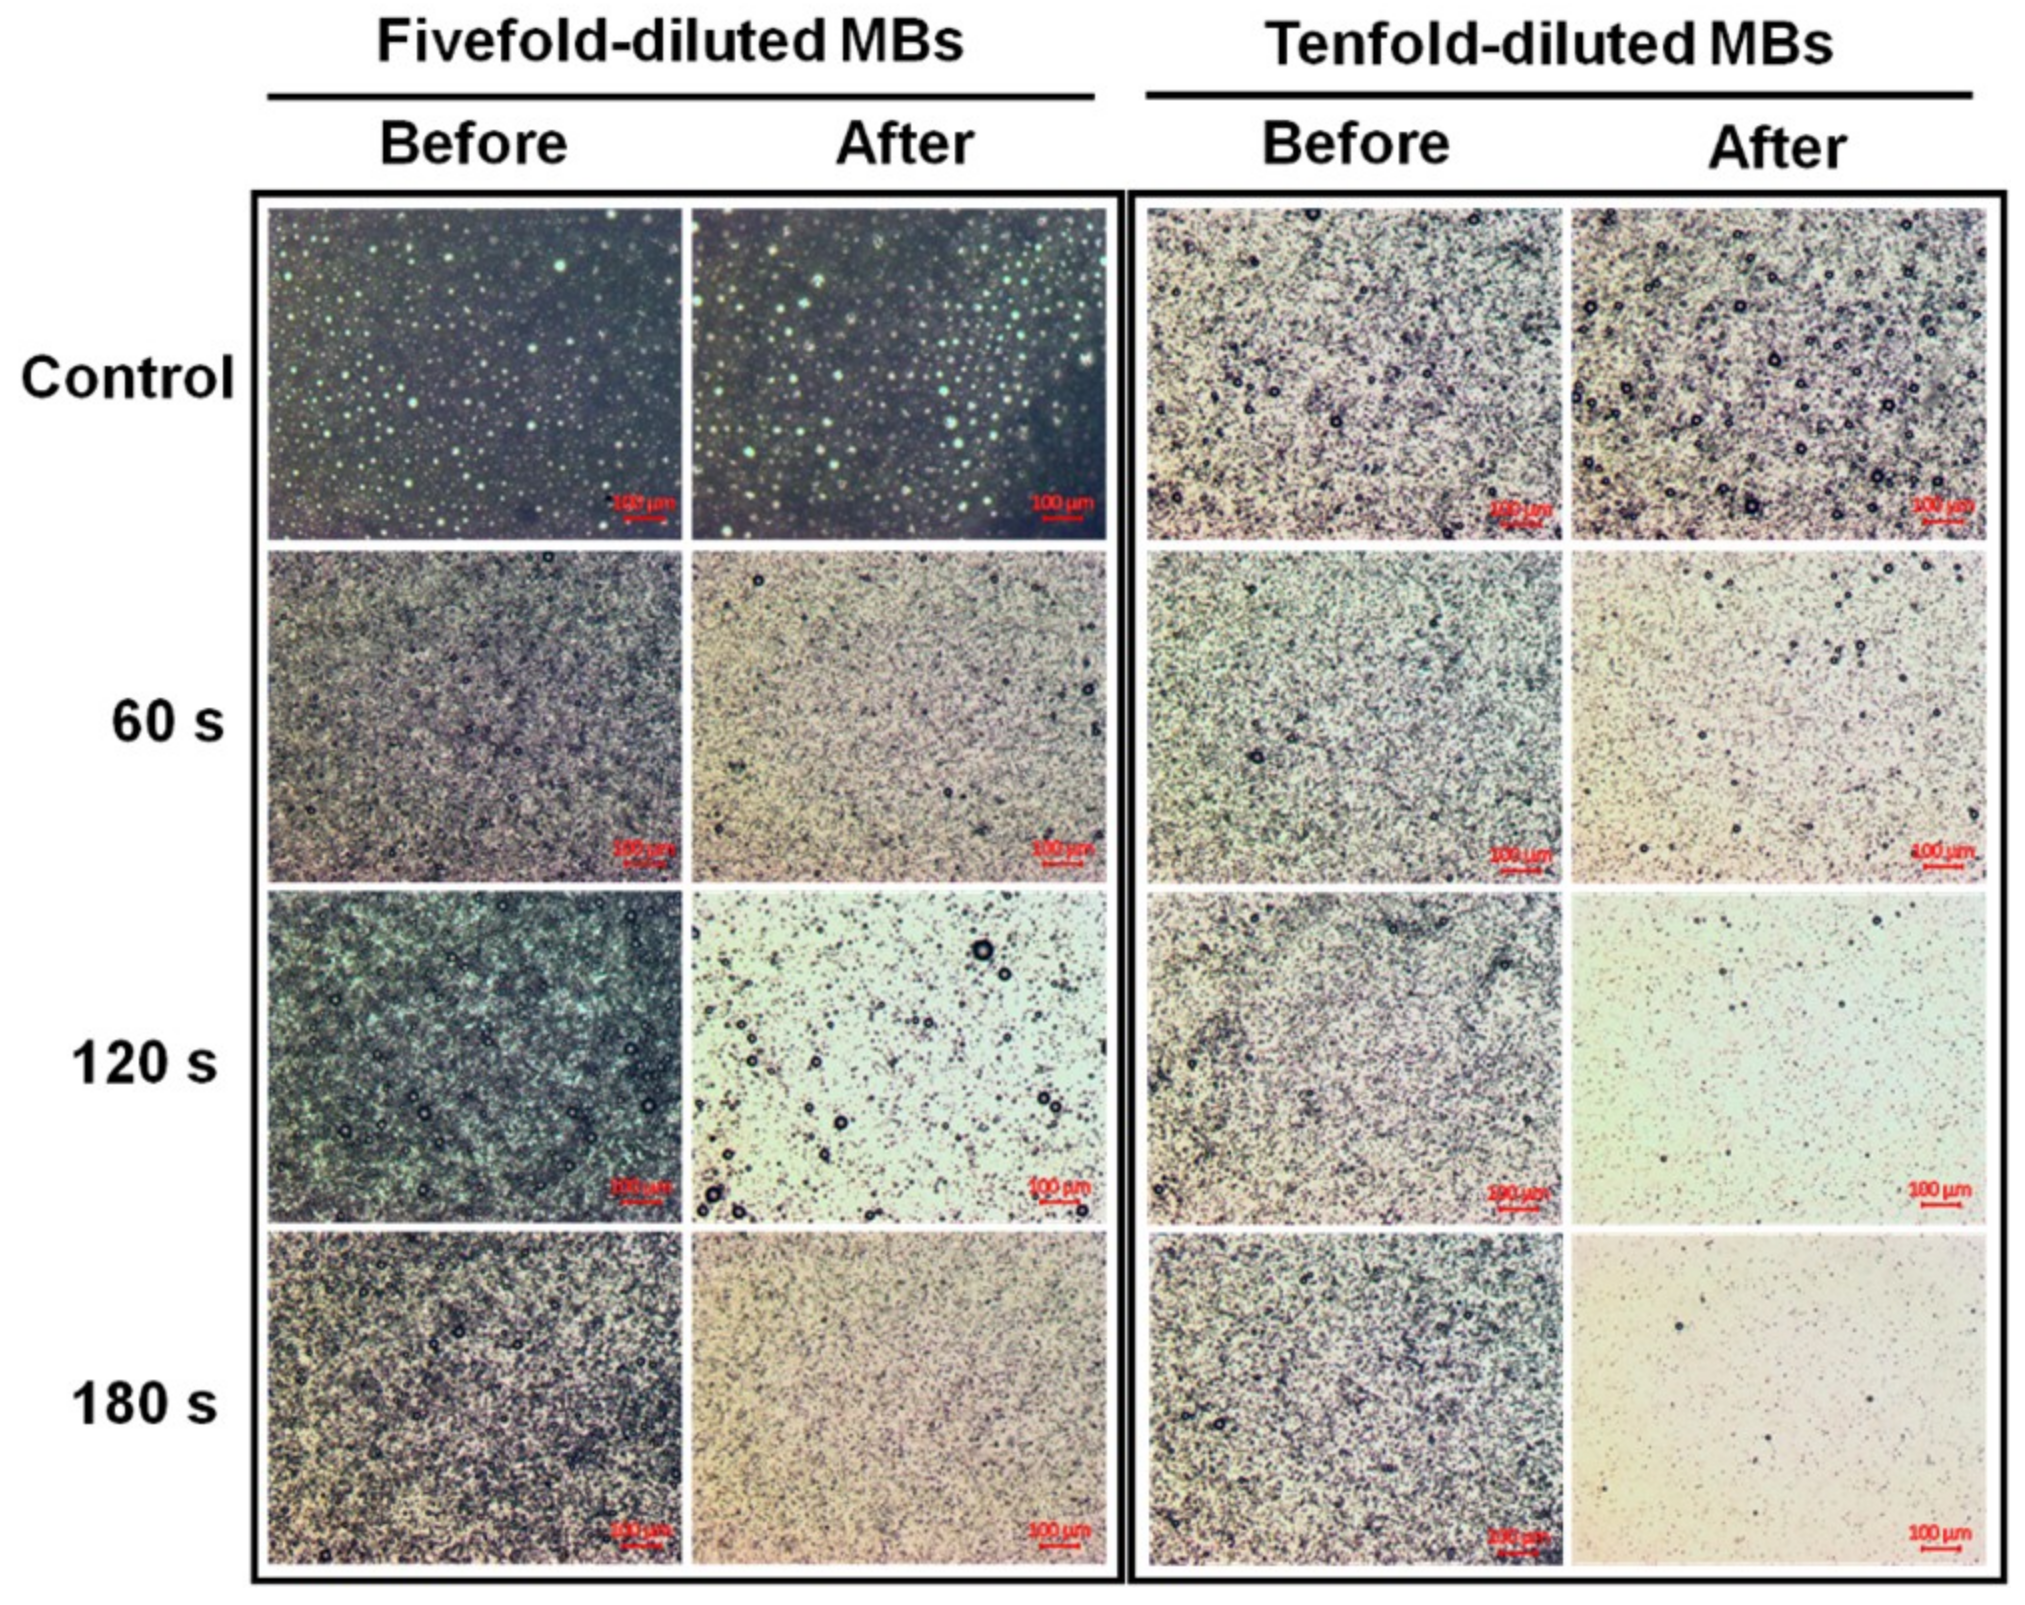

2.2. Laser-Induced MB Disruption

3.1. Laser-Induced MB Disruption